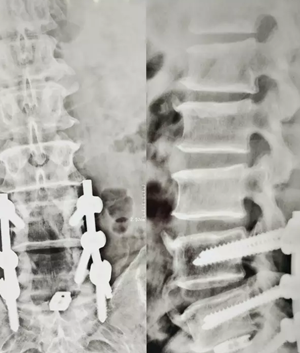

10月7日上午9点,王先生被推入手术室开始手术。由胡玉华院长、李龙付副主任为他进行“腰4/5 、腰5/骶1椎间盘突出症+全椎板切除减压钉棒融合内固定术”。手术过程中并未出现状况,3个半小时以后,手术顺利的完成了。随即被送入了ICU病房进行监护。经过一段时间的护理,王先生已经恢复的很好了。

(术后)